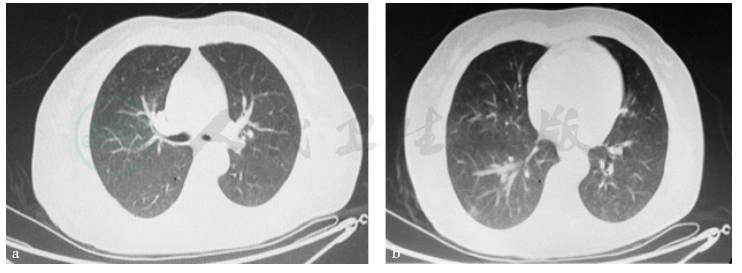

图2 胸腹盆平扫+增强CT

引自:主编:.消化系统疑难疾病诊疗思维及病例解析.第1版.ISBN:978-7-117-28669-5

患者呕吐,需要排除所有可能的器质性疾病后,才考虑功能性疾病所致。胃镜、肠镜、全消化道造影、肿瘤标志物、胸腹盆平扫及增强CT可以排除消化道器质性疾病。肝肾功能、血糖、甲状腺功能正常,可以排除常见代谢和内分泌系统疾病。患者病史较短、急性起病,无口干、眼干、皮肤发紧、皮肤红斑、关节疼痛等症状,且风湿全套检查未见异常,可排除风湿免疫疾病所致呕吐。反复追问病史得知,患者并无药物服用史、毒物接触史。患者为青壮年女性,出现严重的肺部感染,且伴有言语不清、吞咽呛咳等症状,应考虑颅脑病变,特别是延髓病变所致。当地医院颅脑MRI虽未见异常,在患者病情加重时应复查。复查颅脑、颈髓MRI提示延髓低信号病变,结合患者脑脊液APQ-4Ab阳性。最终明确诊断。